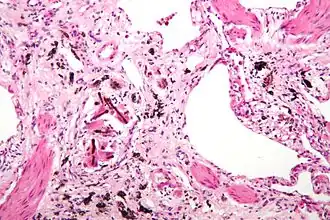

La pneumoconiose est un ensemble de maladies pulmonaires caractérisées par des altérations causées par l'inhalation et la fixation dans le poumon de particules solides. Certaines de ces maladies provoquent une fibrose du poumon, et d'autres non.

La réaction du poumon aux poussières minérales dépend de nombreuses paramètres, parmi lesquels la taille, la forme, la solubilité et la réactivité des particules. Par exemple, il est peu probable que les particules de tailles supérieures à 5 à 10 μm atteignent les alvéoles pulmonaires, tandis que les particules de moins de 0,5 μm pénètrent dans les alvéoles et en sortent, souvent sans dépôt ni blessure importants. Les particules de 1 à 5 μm de diamètre sont les plus dangereuses car elles se logent dans les alvéoles pulmonaires ou à la bifurcation des bronchioles. La poussière de charbon est relativement inerte et de grandes quantités doivent être déposées dans les poumons avant que la maladie pulmonaire soit cliniquement détectable. La silice, l'amiante et le béryllium sont plus réactifs que la poussière de charbon, ce qui entraîne des réactions fibrose à des concentrations plus faibles. La plus grande partie de la poussière inhalée est emprisonnée dans la couverture de mucus et rapidement expulsée du poumon par le mouvement ciliaire. Cependant, certaines des particules sont affectées par les bifurcations des canaux alvéolaires, où les macrophages s'accumulent et engloutissent les particules piégées. Le macrophage alvéolaire pulmonaire est un élément cellulaire clé dans l'initiation et la perpétuation de la lésion pulmonaire et de la fibrose. De nombreuses particules activent l'Inflammasome et induisent la production d' IL-1 . Les particules les plus réactives déclenchent la libération par les macrophages d'un certain nombre de produits qui induisent une réponse inflammatoire et initient la prolifération des fibroblastes et le dépôt de collagène. Certaines des particules inhalées peuvent atteindre les vaisseaux lymphatiques soit par drainage direct, soit dans des macrophages en migration, provoquant ainsi une réponse immunitaire aux composants des particules et / ou aux protéines qui sont modifiées par les particules. Ceci conduit alors à une amplification et une extension de la réaction locale. Le tabagisme aggrave les effets de toutes les poussières minérales inhalées, plus encore avec l'amiante qu'avec toute autre particule.